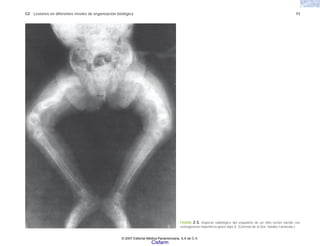

FIGURA 2-3. Aspecto radiológico del esqueleto de un niño recién nacido con

osteogénesis imperfecta grave (tipo I). (Cortesía de la Dra. Sandra Carnevale.)